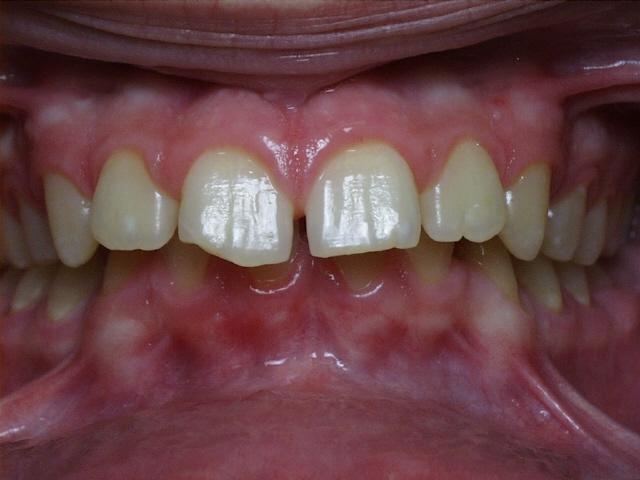

Severe crowding with a crossbite of the front teeth.  Treatment time was 18 months.  This case required the extraction of four permanent teeth.  The molars were class 1 (upper and lower molars met properly at start of treatment).  This patient's teeth are discolored in the final photo because of poor oral hygiene while wearing braces.